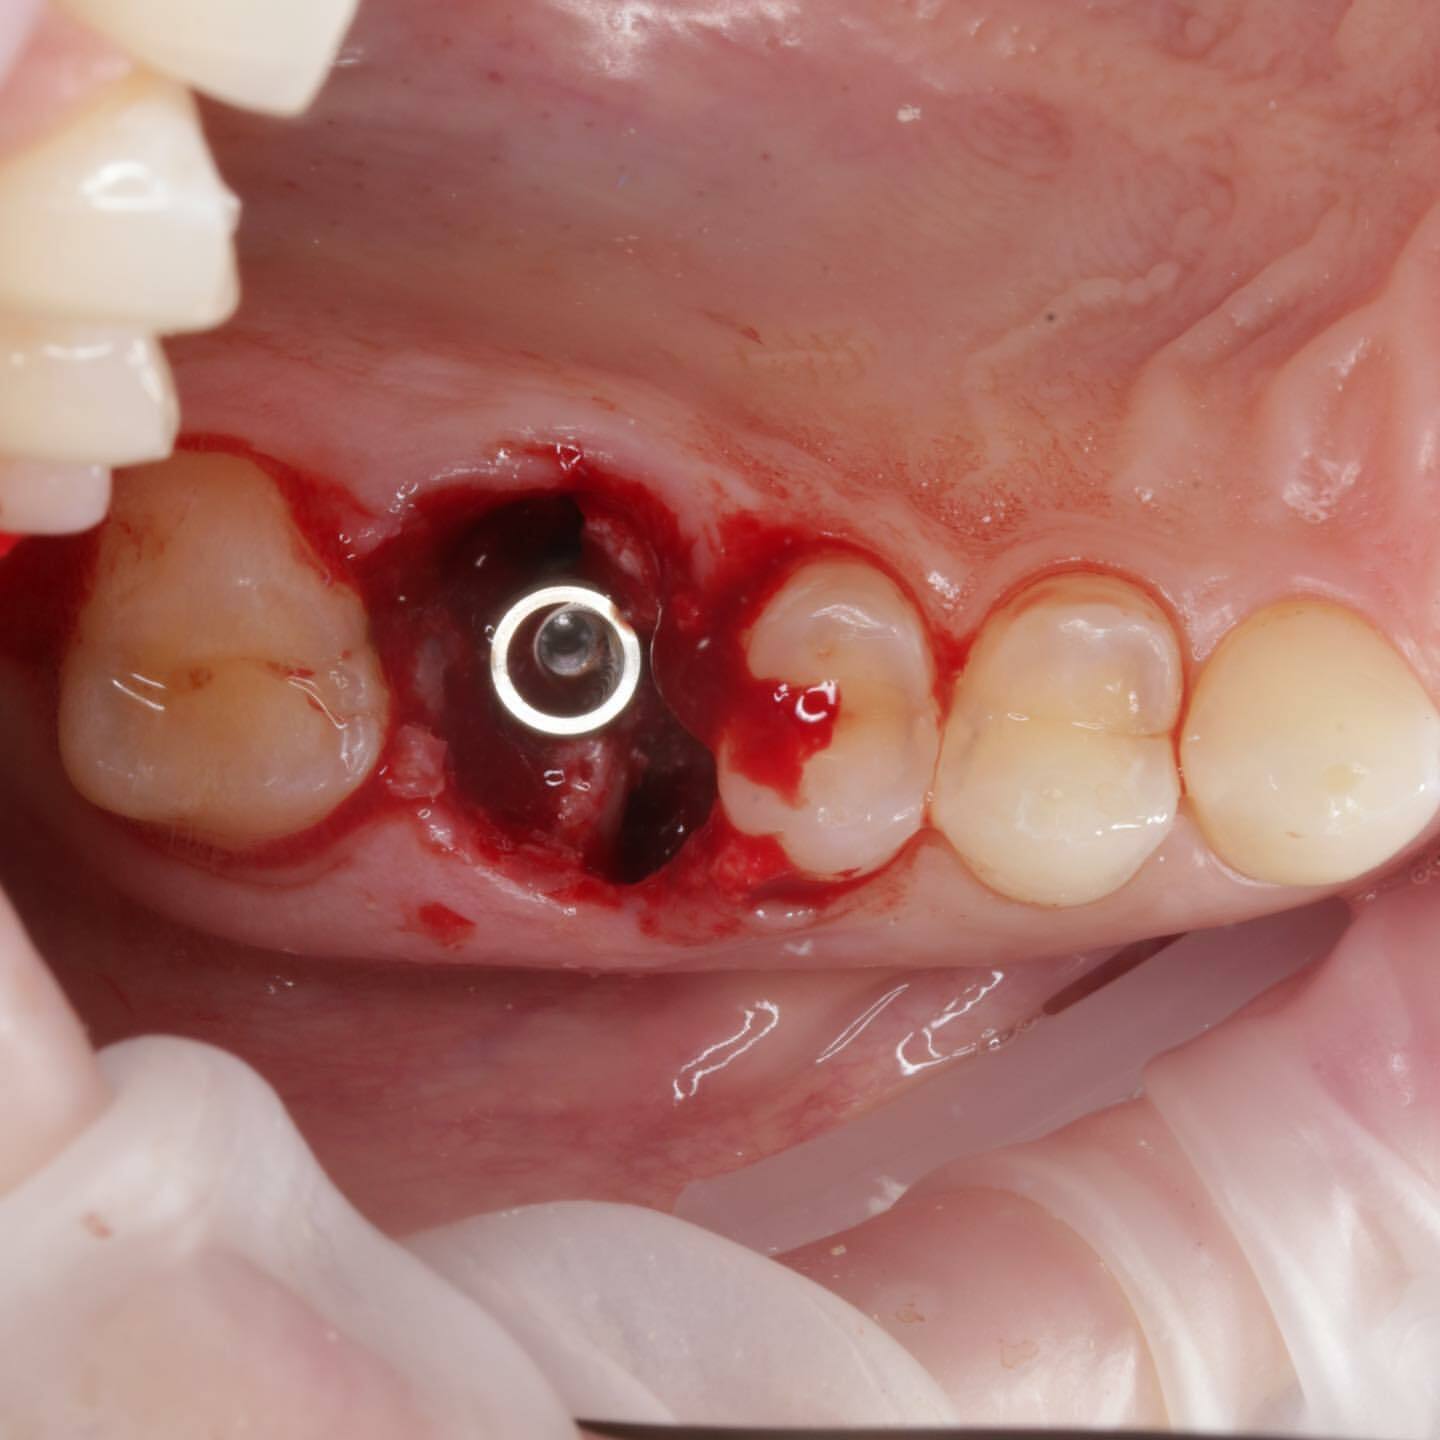

Период «без зуба» существенно сокращается или вовсе отсутствует. Так как в классическом протоколе после удаления мы ждём 2-3 месяца, потом ставим имплантат и ждём его остеоинтеграции 3-4 месяца. Только после этого приступаем к изготовлению коронки.

При одномоментном протоколе мы ускоряем весь процесс на 2-3 месяца! То есть после удаления и одномоментной имплантации мы ждём только 3-4 месяца 🥳

Вместо двух операций (сначала удаление, а спустя два-три месяца имплантация) проводится одна двойная операция. И, соответственно, вместо двух послеоперационных периодов получается один.

🟢 НЕТ ПОТЕРИ КОСТНОЙ ТКАНИ

При классической имплантации в период между удалением и имплантацией костная ткань, так необходимая для успешной приживаемости имплантата, остается без нагрузки, поэтому неизбежно уменьшается в объеме. Одномоментная имплантация позволяет этого избежать.